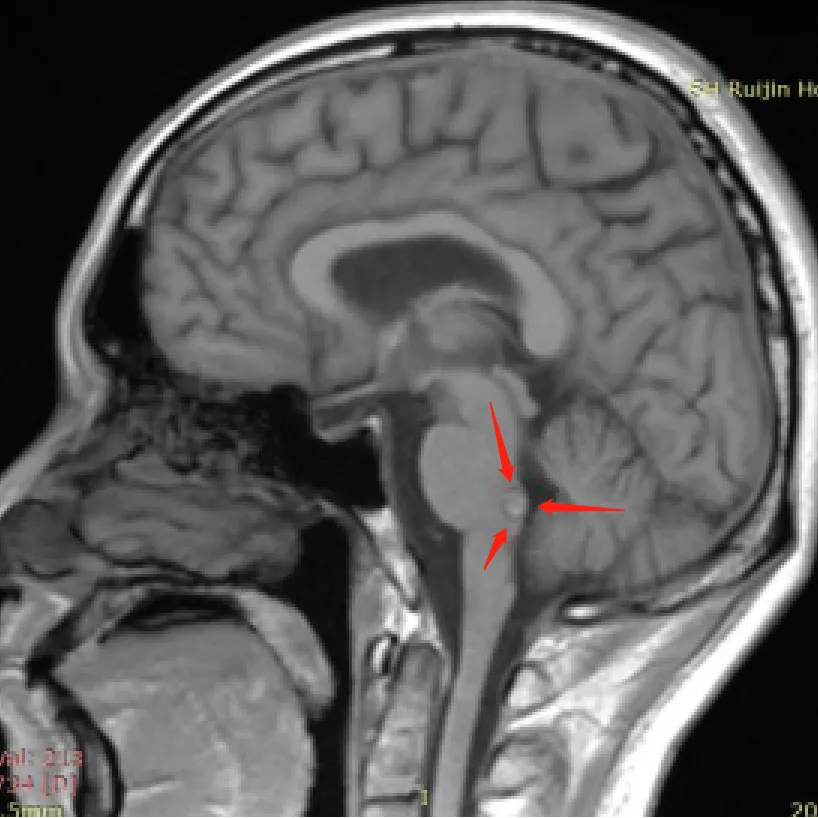

切干净的血管瘤,还会卷土重来吗? 从查出脑干海绵状血管瘤那天起,三个问题就像三座大山:会不会出血?要不要手术?手术切完了还会不会再长? INC巴特朗菲教授曾为一名脑干海绵状血管...

在神经外科领域,脑干海绵状血管瘤是一种让医生和患者都高度警惕的疾病。尤其是已经发生过出血的患者,常常会陷入焦虑和恐惧:为什么是我?、什么时候会再次出血?、我该怎么办?。...